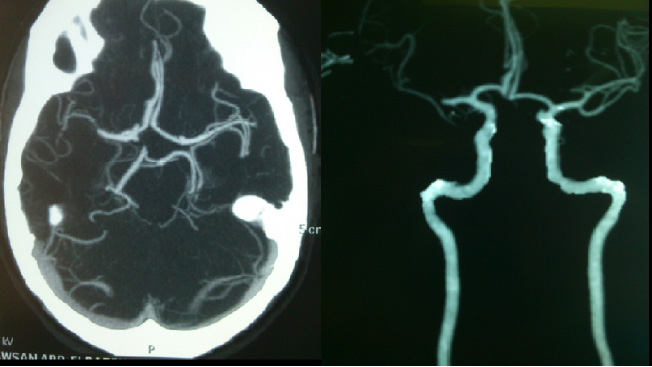

CT Angiography was done after treatment and showed recruitment of the leptomeningeal collaterals despite incomplete recanalization of MCA (Figure 3).

| Figure 3: CTA showing occlusion of right MCA with recruitment of pial collaterals |